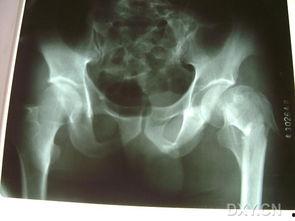

最近在网上看到一个话题,让人不禁好奇起来——股骨颈骨折的图片。你知道,这种骨折可不是闹着玩的,它可是老年人常见的骨折类型之一。今天,就让我带你一起揭开股骨颈骨折的神秘面纱,从多个角度来了解一下这个话题。一、股骨颈骨折是什么?股骨颈骨折,顾名思义,就是发生在股骨颈部的骨折。股骨是人体最长、最粗大的骨头,位于大腿骨的上端,连接着髋骨和膝关节。股骨颈骨折通常发生在老年人,尤其是女性,因为随着年龄的增长,骨骼密度下降,骨头变得脆弱。二、股骨颈骨折的病因1. 外伤:...